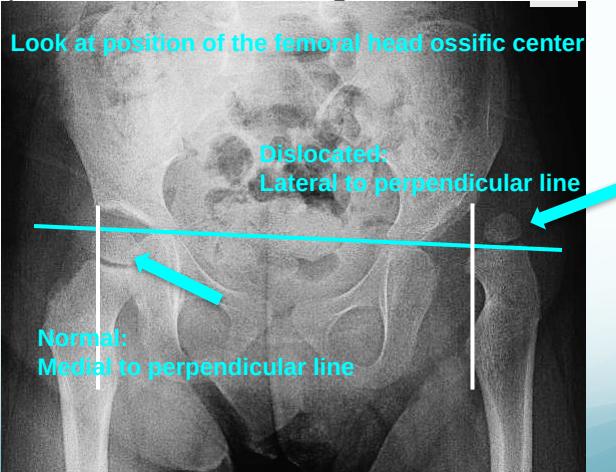

2. Perpendicular Line from Acetabular Edge

- Normal: Femoral head ossific center medial to perpendicular line

- Dislocated: Femoral head ossific center lateral to perpendicular line